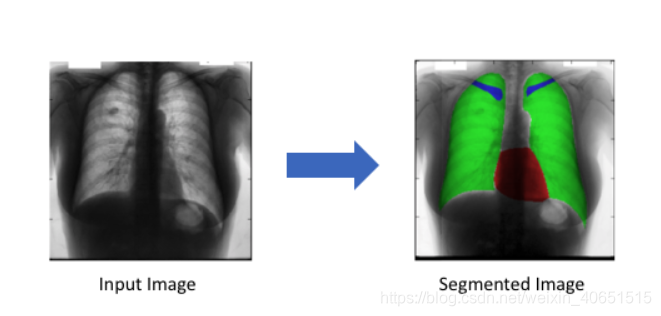

1.2.2 生物医学影像诊断(精准医疗)

这就是本文将要实现的具体应用了。其实现的最终模型可以减少放射科医生的分析时间,为相关疾病的诊疗提供辅助和技术支持。